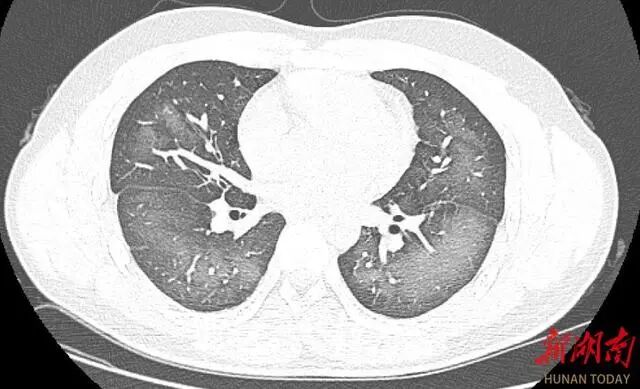

经检查,肺部CT片显示,李林双肺赫然呈现大范围白色样病变,报告提示“白肺”。

“白肺”一般是指重症肺炎在X线或CT检查下的表现,患者肺部呈现一大片的白色状态,往往会出现呼吸困难、呼吸衰竭,严重者还会出现其他脏器功能障碍。

只是喷个防晒喷雾肺部为何会受损?长沙市第三医院放射影像科的接诊医师表示,除了感染、弥漫性肺泡出血综合征等“白肺”最常见的病因外,吸入有害物质如粉尘、喷雾等,也可导致肺部出现大范围白色样病变。这名年轻的患者就是因为使用不当,吸入了一部分防晒产品进入肺部,导致“白肺”的发生。